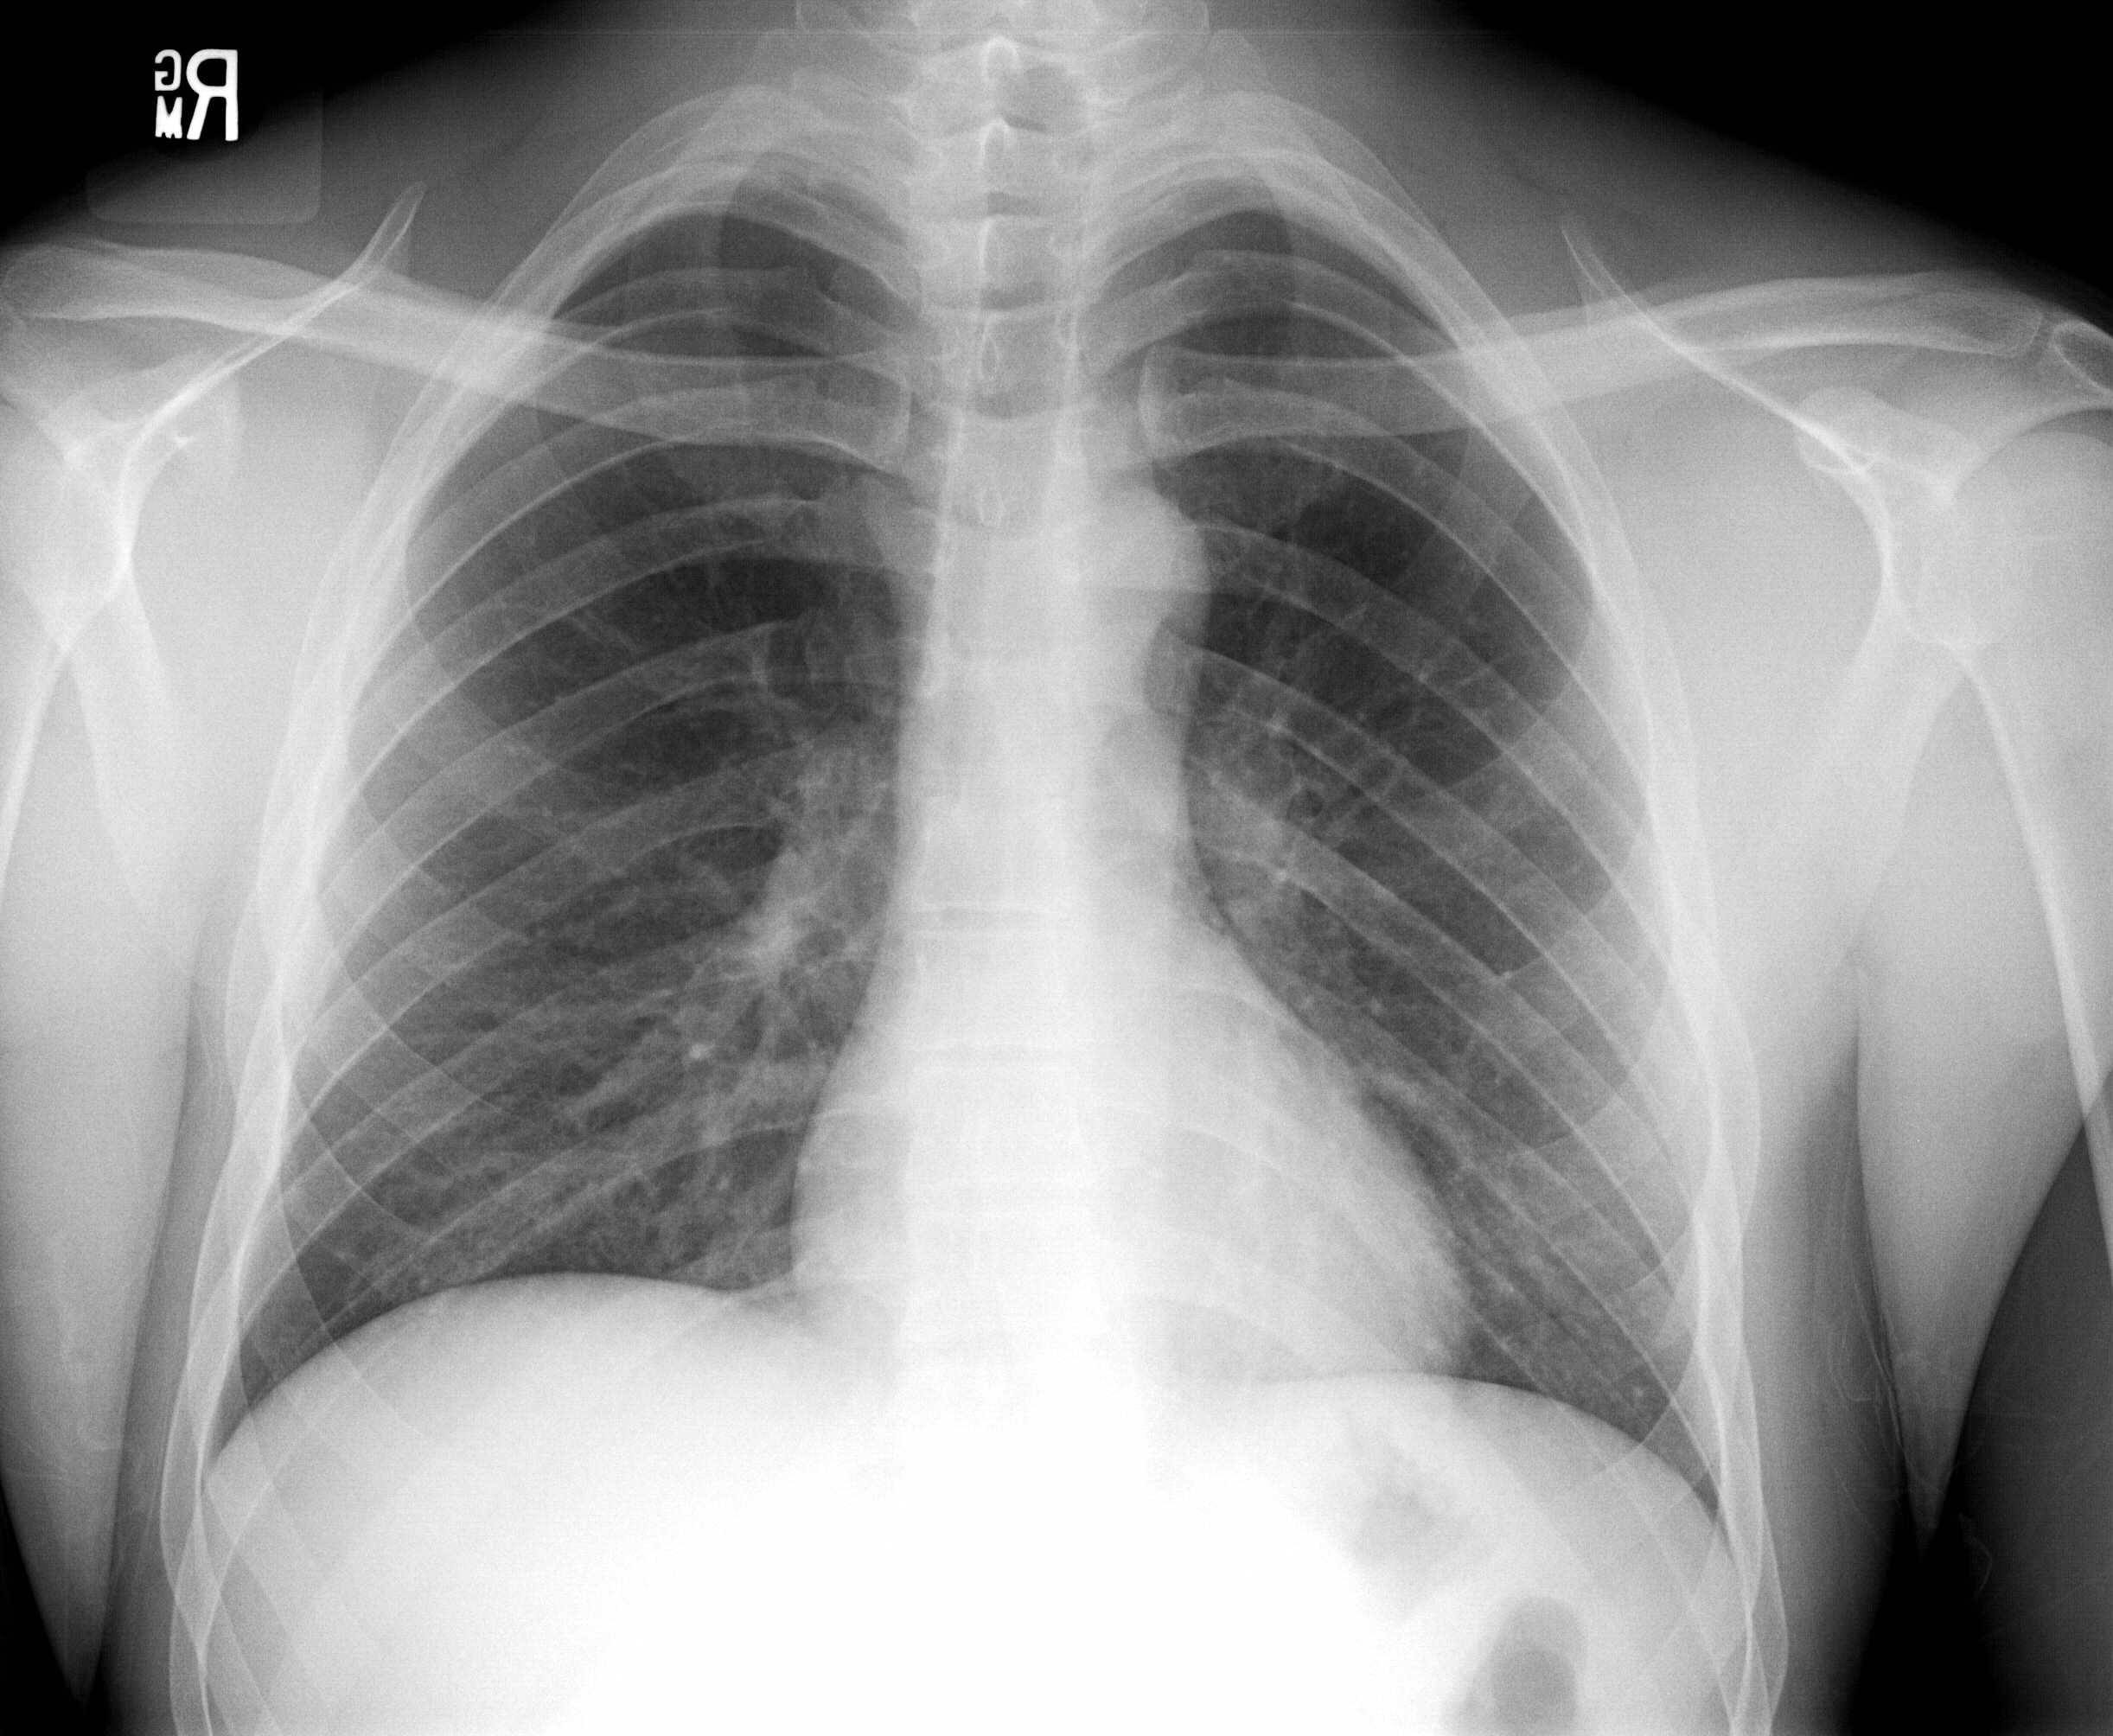

Patient name

VAUGHAN^DEAN

Patient ID

345345

Patient sex

M

Study date

20110310